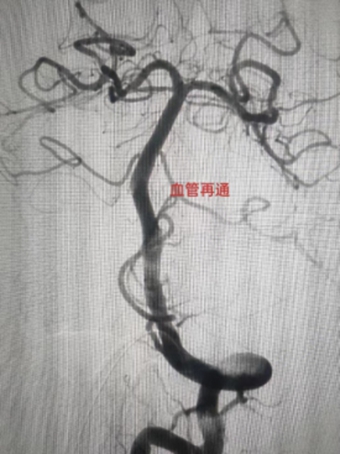

“时间就是大脑”,全脑一旦血供中断,6秒内神经细胞代谢受影响,10~15秒内意识丧失,2分钟内脑电活动停止,持续5分钟以上则脑细胞发生不可逆转的损害,急性脑梗死的治疗就犹如一场与时间的赛跑。近日,商城县人民医院介入手术室内争分夺秒完成了一例急诊取栓治疗实现血管再通,又一次给患者带去生命的希望。

6月7日下午,家住长竹园乡的刘先生突然出现左侧肢体无力,双眼向右侧斜视(凝视),言语不清、口角歪斜等症状,下午3点家属将其送入我院,急诊行头颅CT未见出血,但其右侧颈内动脉末端及大脑中动脉可见高密度征,考虑为大血管病变所致的急性脑梗死,NIHSS评分:14分,mRS评分4分,因无溶栓禁忌,与家属沟通后给予急诊静脉溶栓(阿替普酶,0.9mg/Kg体重)治疗。溶栓大约10分钟左右患者开始出现烦躁,头痛,(NIHSS评分:14分,mRS评分5分)急诊头颅CT未见出血转化,在右侧大脑中动脉供血区出现大片状低密度灶,情况变得更加凶险,卒中团队综合考量认为患者此时急需血管开通治疗以避免脑细胞进一步坏死,再次与患者家属沟通病情后开始急诊取栓治疗。下午3点30分患者被紧急推入介入手术室。

在卒中中心团队的默契配合下,手术顺利取出血栓,实现左侧大脑中动脉完全再通。从动脉穿刺成功到血管完全再通历时仅40分钟。术后患者生命体征平稳,术后1周,患者病情稳定,神志清楚,对话流利,凝视症状缓解,NIHSS评分由14分变为8分。